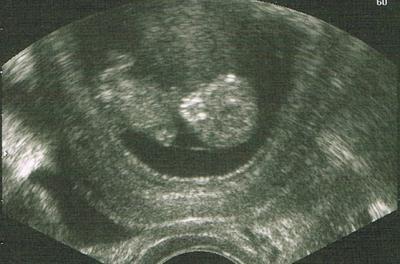

War auch alles in Ordnung, nur leider hat sie wenig gezeigt. Selbst den Herzschlag konnte ich nicht sehen. Sie meinte aber, dass sie den gesehen hat. Und das Kleine ist zeitgemäß gewachsen.

Sie meinte, es entspricht von der Größe her eher 10+6 und nicht 10+2, aber das kann auch ein Messfehler sein. So oder so: es ist gewachsen.

Grad noch die Größe im Mutterpass gelesen: 3,57 cm ;)